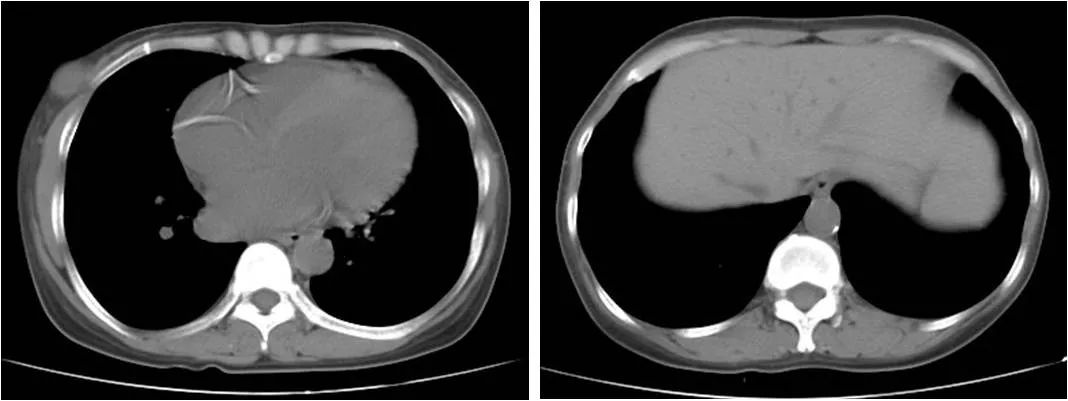

评估患者异位钙化情况:冠状动脉及主动脉可见钙化(图1),同时患者有身高缩短、骨痛等症状,PTH控制不理想,需要调整SHPT药物。

图1 患者胸部CT平扫提示冠状动脉钙化(左)以及腹主动脉(右)钙化